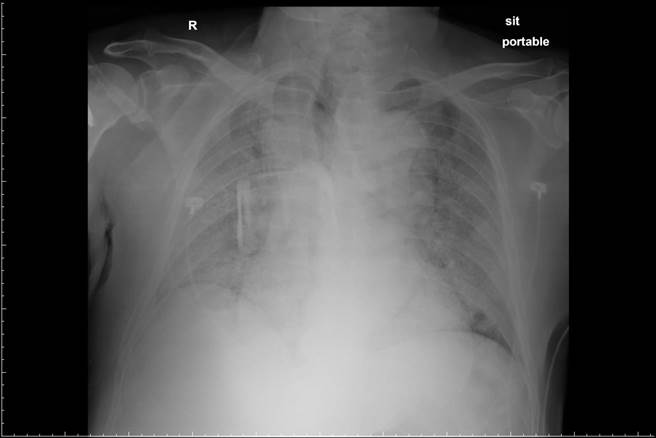

柯世祐醫師今稍早在個人臉書發文,分享兩張X光片表示,一名近70歲的男性有咳嗽症狀,並伴隨呼吸急促、喘,該男子因有萬華接觸史,家人趕緊將他送至醫院急診,醫護人員隨即幫其做檢查,並照X光,發現肺部呈現大片白色,必須馬上插管治療。

因男子及家屬不願插管及急救,醫護人員只好給予高濃度的氧氣及藥物,沒想到短短不到24小時,該男子就病逝了。柯世祐醫師說,這種在急診室喘到病逝的病患只會愈來愈多,病患一個人默默地在急診嚥下最後一口氣,沒有一點聲響、沒有一點回音,也沒有人陪伴,淹沒在新冠病毒的洪流中,宛如我們看到的國外慘況。

該男子的肺部因染疫,呈現整片白色。(圖/翻攝自柯世祐臉書)